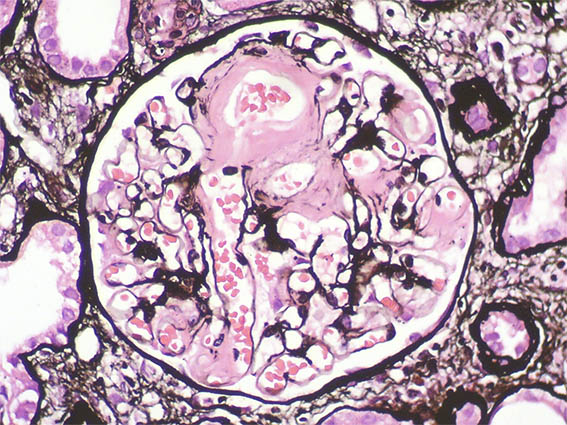

Figura 11. Plata-metenamina, X400.